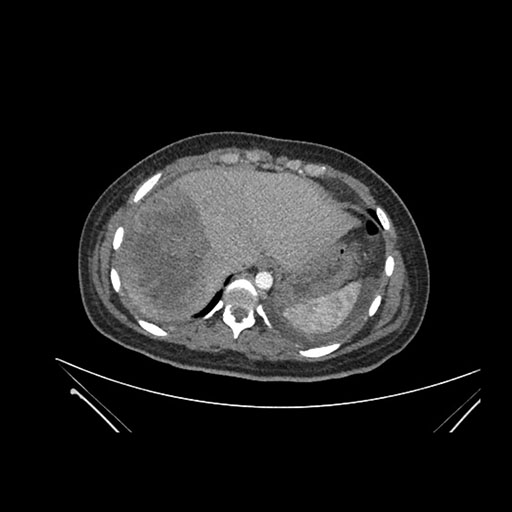

Imaging Analysis

Look through the patient's CT scan to identify any areas of concern for the necessary procedure.

Coronal Arterial

Based on initial findings, which issue(s) would you be most concerned about?